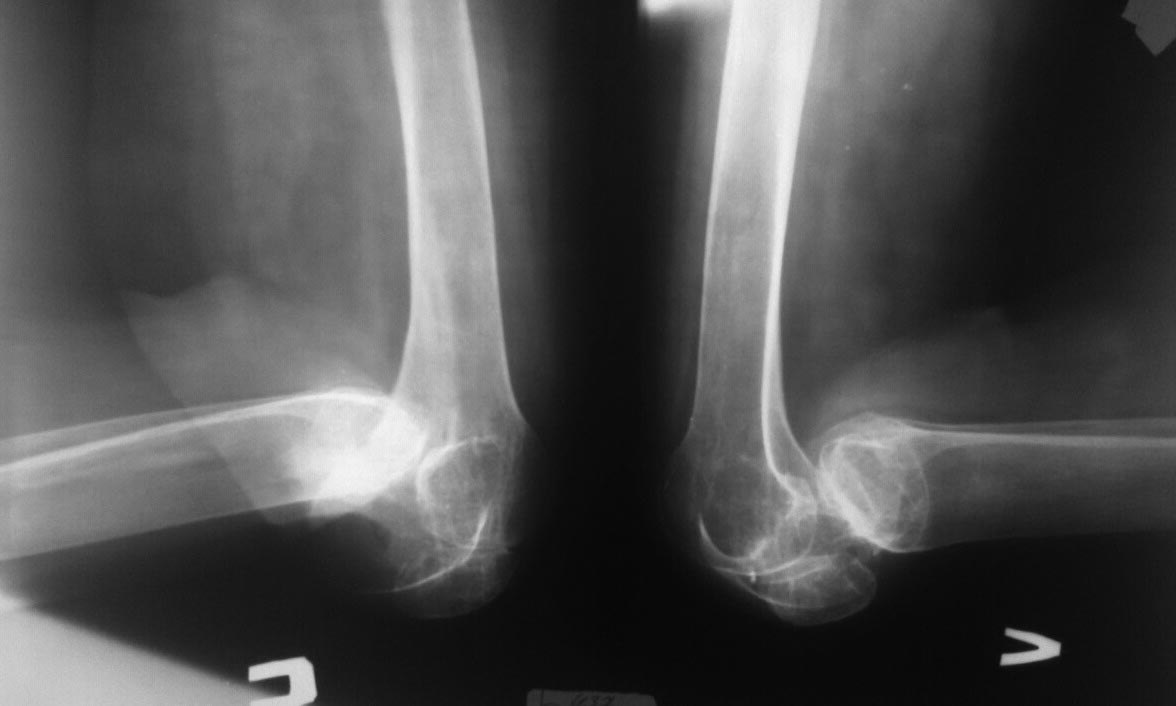

Девочка 16 лет, 4 года назад по поводу ожога пламенем тяжелой степени обеих нижних конечностей она лечилась в сельской больнице, несколько этапов аутодермопластики, и в настоящее время обратилась в отделение травматологии и ортопедии за помощью.

Если честно, такую категорию больных никто давно не помнит, 4 года как она не ходит, материальная сторона больной, естественно, не может позволить ей куда то выехать и лечиться. Наш диагноз: Двухсторонняя постожоговая контрактура коленных суставов, вывих голеней кзади.

Фото и рентген снимки прилагаются. Мы думали о метаплазии по Вредену, Капсулотомии по Вильсону, Резекции суставных поверхностей и артродезе, можно в аппарате Илизарова, но во всех случаях сомнения и вопросы:

Сможем ли одномоментно вывести конечность в более правильное положение, не рановато ли с артродезирванием в 16 лет? Буду рад и признателен советам форума